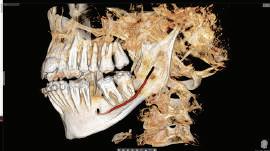

Examinarea parodontală a relevat sângerări generalizate la sondare și adâncimi de sondare de până la 9 mm la molarii maxilari și mandibulari, cu multiple furcații implicate la fiecare molar (fig. 2-7). Prezenta mobilitate multiplă de clasa I la dinții posteriori și de clasa II la dinții nr. 16 și 21 (molarul prim maxilar drept și incisivul central maxilar stâng).

Parodontologul a decis să evalueze dintele nr. 16 în privința PRS, deoarece acesta era molarul cel mai afectat parodontal care urma să fie tratat și menținut pe arcadă (fig. 2 și fig. 8). Acest dinte (molarul prim maxilar drept = scor 1) prezenta adâncimi de sondare de 7 mm (scor 1); trei invazii totale de furcație (scor 3) (mezial [furcație de grad II], vestibular [furcație de grad I] și distal [furcație de grad II]); și mobilitate de clasa II (scor 2). Valoarea totală a PRS pentru dintele 16 a fost de 8, reprezentând un prognostic „rezervat”. Pe baza acestui scor, probabilitatea de a nu pierde niciun dinte din cauza bolii parodontale timp de 15 ani a fost de 81%, iar pentru 30 de ani probabilitatea a fost de doar 56% (fig. 9).

2-4. Imagini înainte de tratament: lateral dreapta (fig. 2), frontal (fig. 3) și lateral stânga (fig. 4). Notă: Molarul prim maxilar drept (dintele 16) (fig. 2) ar fi identificat ca fiind molarul cel mai afectat parodontal care era planificat să fie menținut.

Figurile:

5, 6. Imagini ocluzale înainte de tratament: maxilar (fig. 5) și mandibulă (fig. 6).

7. Rx periapicale înainte de tratament.

8. Rx periapicală a molarului prim maxilar drept (identificat ca fiind molarul cel mai afectat parodontal care era planificat să fie menținut pe arcadă).